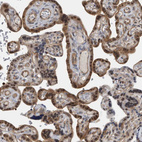

Immunohistochemistry analysis in human small intestine and skeletal muscle tissues using HPA023739 antibody. Corresponding NAPRT RNA-seq data are presented for the same tissues.